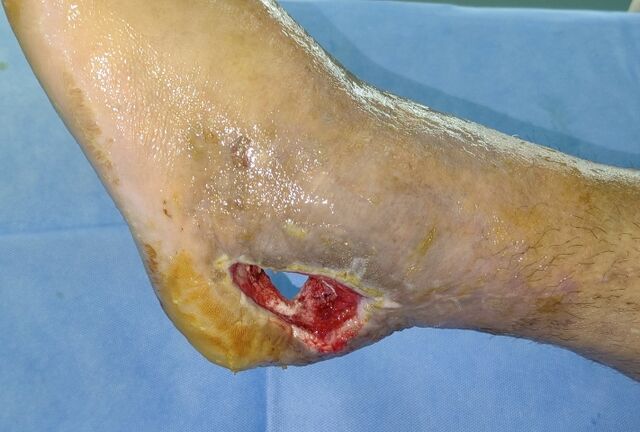

另一患者跟骨骨折术后感染

内外侧贯通创面

彻底清创后

伤口贯通

抗菌素骨水泥填充覆盖